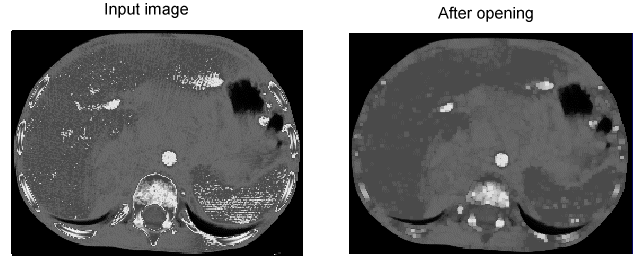

Opening

An opening operator first performs an erosion on the input image and then performs a dilation on the result in order to generate the output image. Opening an image removes small amounts of bright pixels and then enhances the remaining bright features:

Image Processing Morphology Theory Grey Scale Morphology Opening

Both opening and closing operators tend to preserve the size and shape of large features while affecting the size and shape of small features.